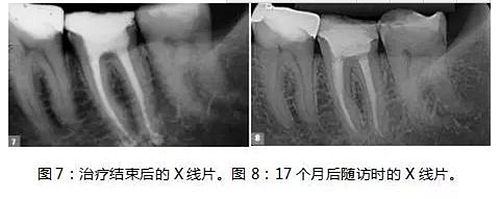

制備MTA-FILLAPEX糊劑并用主牙膠將其導(dǎo)入到根管內(nèi)(圖6)。使用攜熱器(Touch’n Heat, Kerr))除去過(guò)量的糊劑,熱垂直加壓。髓室用光固化復(fù)合樹(shù)脂密封,病人回到她的牙科醫(yī)生處,完成最終修復(fù)體的制作(圖7)。

17個(gè)月后,患者回訪, X線片結(jié)果顯示治療效果相當(dāng)成功(圖8),患者沒(méi)有陽(yáng)性的癥狀和體征,牙齒的生理功能正常,根尖位置正常,根尖周多余的MTA-FILLAPEX已經(jīng)吸收干凈了。